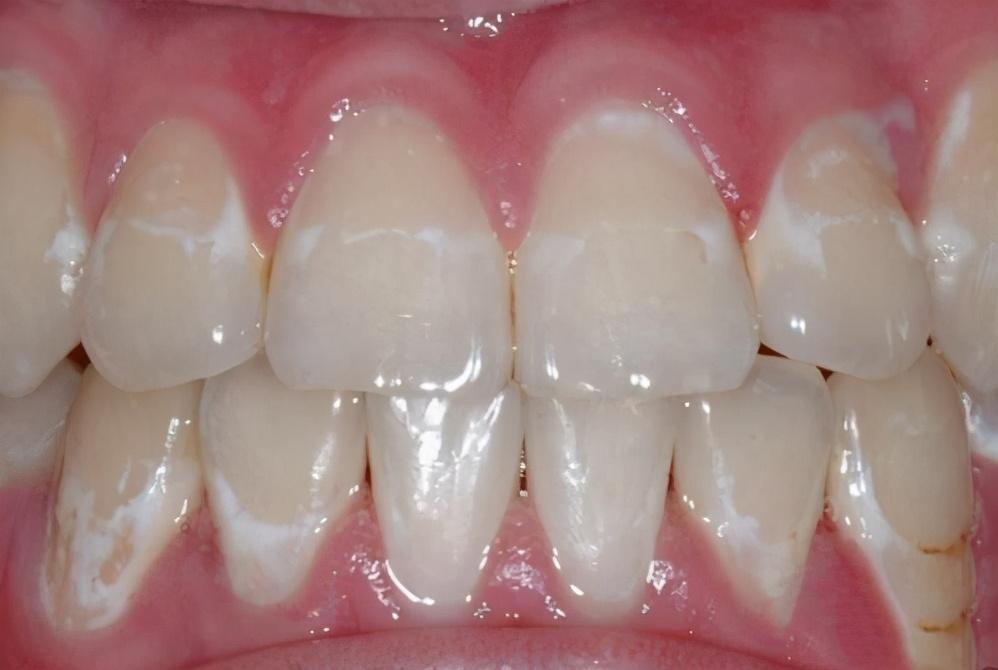

上面我们讲过,咀嚼时牙疼,很可能是已经得了蛀牙。但蛀牙是有过程的,在蛀牙初期,往往都是有征兆的。比如牙齿上出现的黑线、白斑,都是蛀牙的征兆。

这种迹象,在儿童身上尤为明显。所以当爸妈们看见孩子牙齿上有黑线、白斑,建议尽快预防,以免真的出现蛀牙,到时候就只能补牙了。